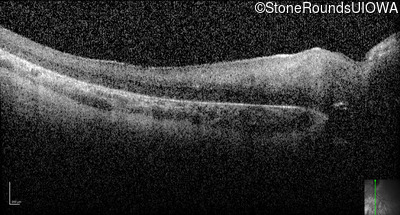

Optical Coherence Tomography - Left -

Light Perception

Exemplar

Expanded OCT Stack

×